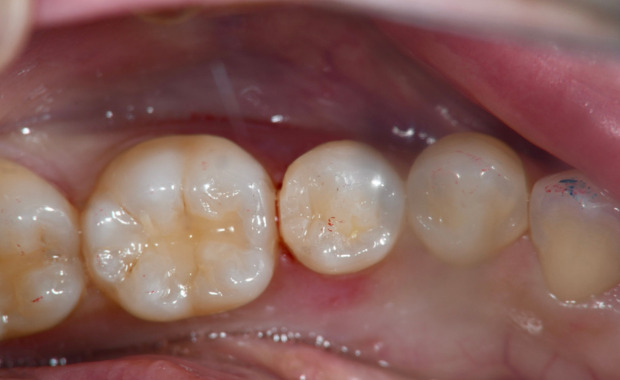

虫歯治療風景

虫歯になってしまうと自然に治ることはありません。 初期の虫歯はすぐに治せますが、放置し進行してしまった虫歯は痛みが伴い、治療期間も長くなります。 そのため、早期発見・早期治療がとても大切です。 当院では、“歯医者に対する不安”を、少しでも和らげ、安心した状態で治療を受けていただける様に、治療の前には、必ず問診の時間と資料取りの時間を設けております。患者さまの実際のレントゲン写真やお口の写真を用いて、正しい情報の提供と治療説明を十分に行い、ご納得いただいた上で治療を行います。